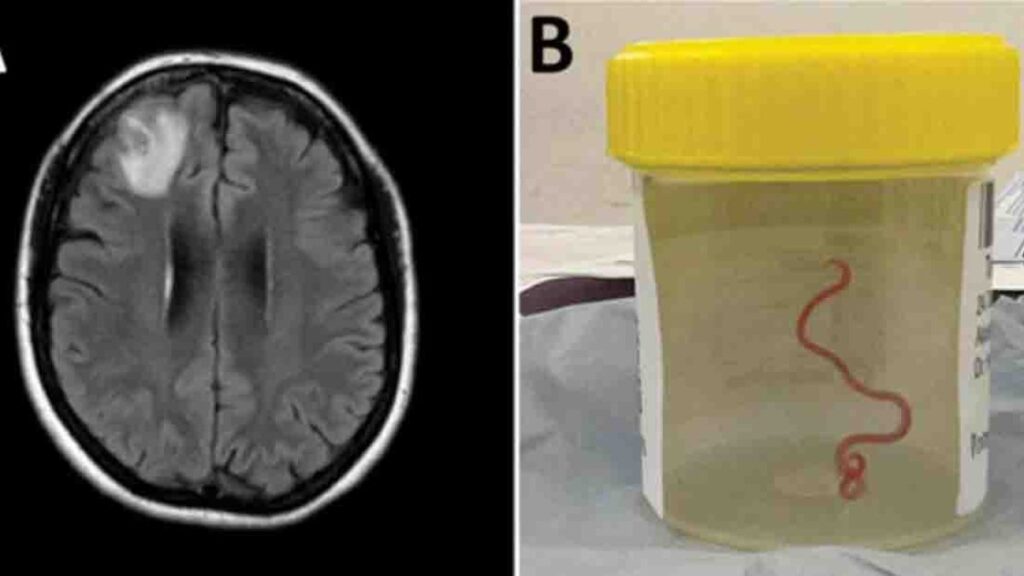

En 2022, la paciente se sometió a una resonancia magnética tras experimentar trastornos en la memoria y depresión. Las imágenes del cerebro de la paciente revelaron que la mujer tenía una lesión atípica en el lóbulo frontal derecho.

Un neurocirujano del Hospital de Canberra exploró la anomalía y fue entonces cuando se encontró la inesperada lombriz intestinal de ocho centímetros.

El parásito fue extraído, vivo y retorciéndose, de la paciente durante de una cirugía cerebral, de la que no se precisa la fecha, y actualmente la mujer continúa siendo examinada por el equipo de especialistas en enfermedades infecciosas y cerebro.